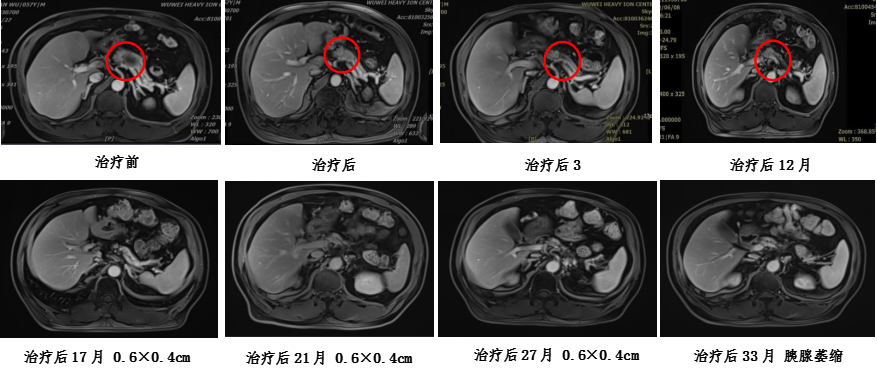

4、治疗方案:胰腺癌碳离子放疗,仰卧位三野轮照总剂量:41.4GyE,4.6GyE/fx;俯卧位PTVboost予以局部推量18.4GyE/4fx,4.6GyE/fx,总处方剂量:PTV 59.8GyE/13fx。治疗期间联合尼妥珠单抗注射液 400mg ivgtt d1周方案+吉西他滨 2.0g ivgtt d1、d8化疗。 治疗过程顺利,未出现明显不良反应,治疗后复查腹部MR提示:胰腺病灶缩小,疗效评价为PR。

5、碳离子治疗计划剂量云图及疗效评估: